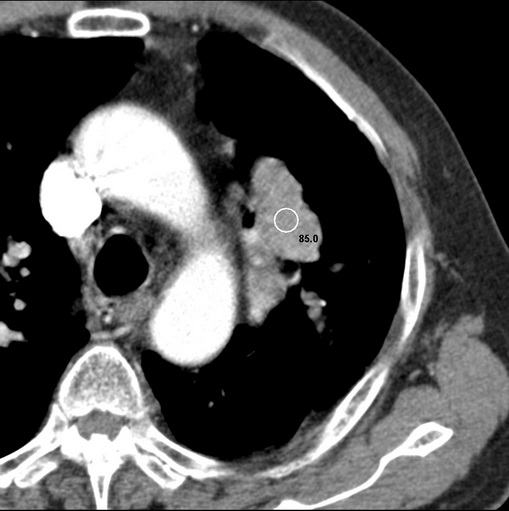

肿块贴近左肺门,包绕左上肺动脉,形态不规则。肿块增强扫描中度强化。纵膈内主动脉弓左旁间隙、气管隆突前、下间隙见多枚淋巴结影。综上考虑左侧中央型肺癌可能性大。图片没有完整上传,尤其是左肺上叶支气管分支层面没有上传,因此不好判断是叶支气管中断还是段支气管中断。另外,下图红色部分所示是“黏液支气管征”吗?